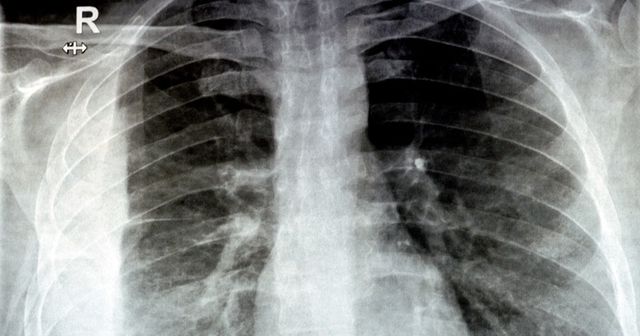

기사의 이해를 돕기 위한 사진 / Tamer A Soliman-shutterstock.com